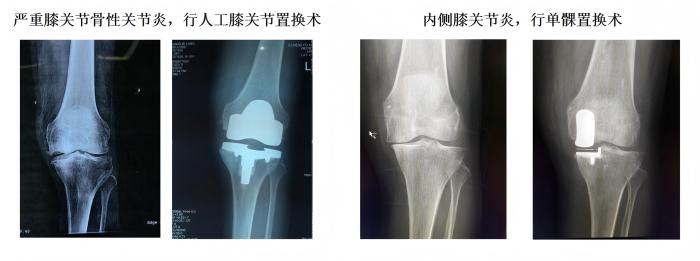

1、常规完成复杂全髋、膝关节置换手术(水泥型、生物型)、单髁置换手术、胫骨高位截骨手术、复杂保髋手术、股骨头坏死综合治疗、高龄老人髋部骨折综合治疗。

学科简介:伦理片 骨科是集医疗、教学、科研的重点科室,2018年评为中国创伤救治中心建设单位,2019年评为福建省骨科联盟成员单位、厦门市医学优势亚专科。科主任个人获得厦门市政府拔尖人才,厦门市劳模等荣誉。目前设有关节运动医疗组、骨折创伤医疗组、脊柱医疗组、小儿骨科医疗组,常规开展髋关节、膝关节置换,单髁置换,反肩置换,髋膝关节翻修术,胫骨高位截骨矫形,椎间孔镜髓核摘除、脊柱UBE镜下融合,肩关节镜肩袖修复、膝关节镜前后交叉韧带重建,复杂骨盆骨折、胫骨平台骨折复位固定。于国内外期刊发表专业学术论文累及50余篇,SCI 8篇。